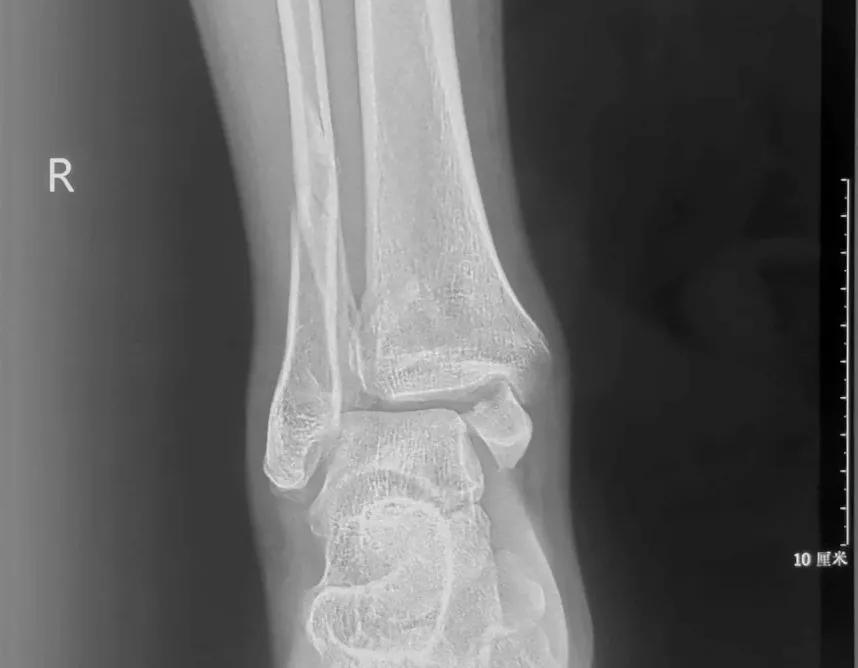

现代医学对手法复位持谨慎态度。在接诊患者后,医生需要通过临床症状、体格检查和影像学检查来全面评估伤情。 对于有脱位的情况,需要急诊手法复位后石膏固定 ,以减轻软组织肿胀和皮肤坏死的风险。更重要的是, 即使复位成功,还需要关注软组织损伤的后续治疗。 如果踝关节内翻扭伤导致的距腓前韧带撕裂没有及时处理,可能会遗留踝关节不稳,甚至引发骨关节炎等后遗症。